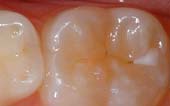

Your pediatric dentist may also recommend protective sealants or home fluoride treatments for your child. Sealants can be applied to your child's molars to prevent decay on hard to clean surfaces.

A sealant is a protective coating that is applied to the chewing surfaces (grooves) of the back teeth (premolars and molars), where four out of five cavities in children are found. This sealant acts as a barrier to food, plaque and acid, thus protecting the decay-prone areas of the teeth.